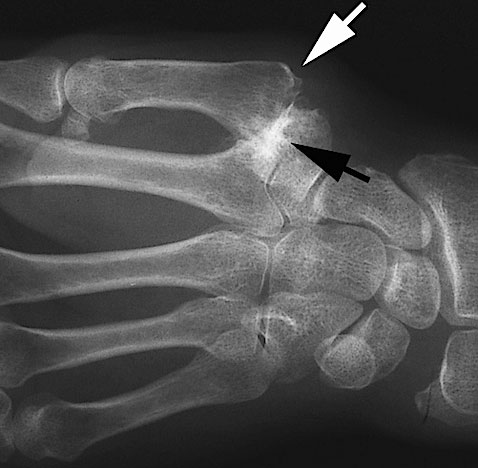

First CMC joint osteoarthritis, also known as thumb base arthritis, is a common and often painful condition affecting the joint at the base of the thumb. This joint is essential for gripping, pinching, writing, and daily hand function. When osteoarthritis develops in this area, even simple tasks such as turning keys, opening jars, texting, or holding a pen can become extremely painful and limiting.

The first carpometacarpal (CMC) joint is the joint at the base of the thumb where the thumb meets the wrist. This joint allows the thumb its wide range of movement, including gripping, pinching, and opposition.

First CMC joint osteoarthritis occurs when the protective cartilage covering this joint gradually wears away. As cartilage thins, the bones rub together, leading to pain, swelling, stiffness, instability, and reduced thumb strength.